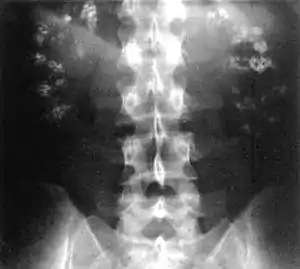

Nephrocalcinosis, once known as Albright's calcinosis after Fuller Albright, is a term originally used to describe the deposition of calcium salts in the renal parenchyma due to hyperparathyroidism. The term nephrocalcinosis is used to describe the deposition of both calcium oxalate and calcium phosphate.[1] It may cause acute kidney injury. It is now more commonly used to describe diffuse, fine, renal parenchymal calcification in radiology.[2] It is caused by multiple different conditions and is determined by progressive kidney dysfunction. These outlines eventually come together to form a dense mass.[3] During its early stages, nephrocalcinosis is visible on x-ray, and appears as a fine granular mottling over the renal outlines. It is most commonly seen as an incidental finding with medullary sponge kidney on an abdominal x-ray. It may be severe enough to cause (as well as be caused by) renal tubular acidosis or even end stage kidney disease, due to disruption of the kidney tissue by the deposited calcium.

| Bilateral nephrocalcinosis seen on an abdominal x-ray | |

Nephrocalcinosis is diagnosed for the most part by imaging techniques. The imagings used are ultrasound (US), abdominal plain film and CT imaging.[10] Of the 3 techniques CT and US are the preferred modalities.